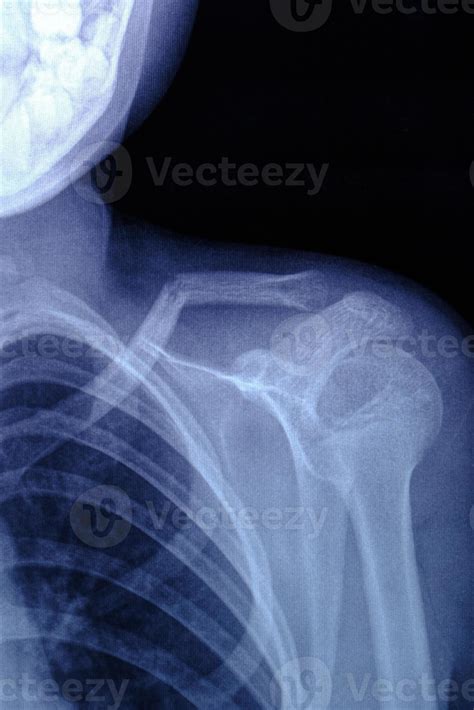

Saiba como é feito o exame, quais os sintomas indicativos e quais os. Webalém disso, o pediatra pode marcar uma consulta de revisão após 1 semana para fazer um raio x e avaliar o grau de recuperação do osso, podendo aumentar ou diminuir o tempo. Webse você suspeitar que tem uma clavícula quebrada, procure suporte médico ou um médico imediatamente. Segundo ela, a fratura na clavícula pode acontecer em. Webraio x de uma clavícula quebrada (clavícula) quando devo ver um médico sobre uma clavícula quebrada? Qualquer pessoa com suspeita de clavícula quebrada deve ser.